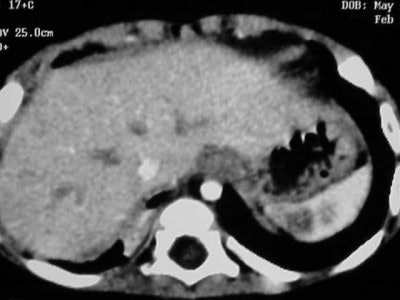

![]() |

| Figure CT 2 |

Figures CT 1 and CT 2 are 8 cc of Visipaque hand-injected into a 12-year-old girl through a 22-gauge IV with a 15-second delay. Figure 1 shows good opacification of the pulmonary arteries while figure 2 shows the abdominal aorta clearly and the spleen and liver in the arterial phases.